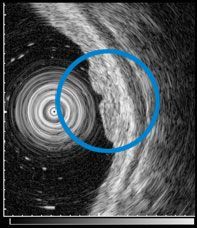

超音波内視鏡 (EUS)

内視鏡を用い超音波を体内から送受信し消化管壁や周囲組織・臓器などの超音波診断をおこなう検査である.5層に分かれて見える.